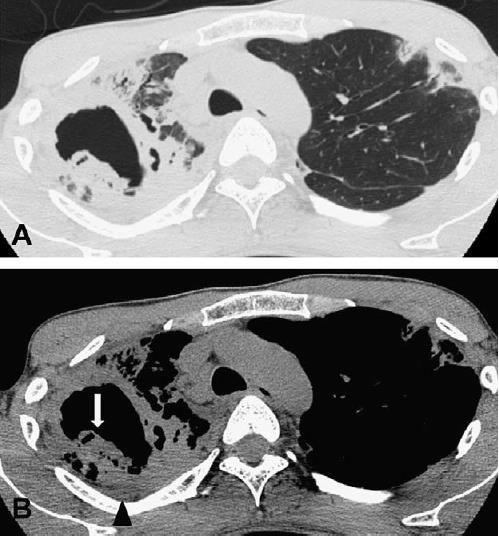

例2:患者肺结核,咯血

图4 胸部CT

图4 胸部CT诊断:肺结核合并曲霉球。

肺结核空洞,长曲霉球,不少见。肺结核空洞内的球会随着体位变动。患者出现反复大咯血,需要手术切除。

例3:患者患有慢性阻塞性肺疾病(慢阻肺病)营养不良,院外不规则口服激素,反复咳嗽,咯血

图5 胸部CT

图5 胸部CT这个空洞乱糟糟的,要考虑鳞癌。但是,患者免疫力低下,空洞里面有网状影,考虑是增生的真菌。有时候肺结核空洞也会这样,但是结核干酪性坏死,里面会死的很彻底,一般是空荡荡的。这种蜘蛛网,曲霉菌病可能性。

结合病史、CT,诊断:慢性坏死性曲霉菌病。

例4:老年男性,因类风湿关节炎口服激素,有慢阻肺病并且长期吸烟,近期发热

入院后给予甲强龙500mg冲击治疗。结果,病情加重。

图6 胸部CT

图6 胸部CT支气管肺泡灌洗液培养:曲霉菌。

空洞周围晕征,空洞内条索影,提示曲霉菌病。